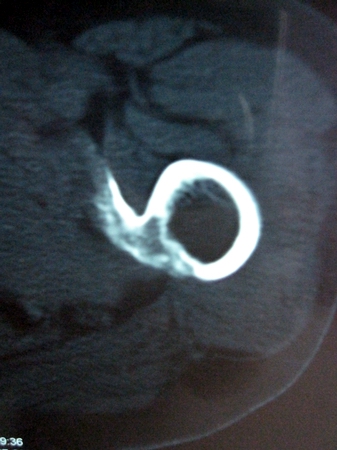

以下是引用lkc8963在2008-12-19 21:19:00的发言:[br]左?右?患侧大转子上移,股骨颈骨质浓杂,髋周见多发条片状骨化影,以小转子为著,多为陈旧性股骨颈骨折后改变并骨化性肌炎.请咨询既往史!